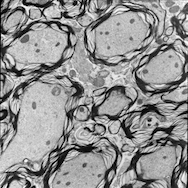

For image analogies based image registration, I have corresponding TEM/Confocal Microscopic image pairs of mouse brains with corresponding regions highlighted by a box. Using the correlative microscopy technique on the mouse brain, I want to localize specific brain regions associated with Pelizaeus-Merzbacher Disease (PMD) and do quantitative assessment of hypomyelination and demyelination in mice. PMD is one of a group of genetic disorders characterized by progressive degeneration of the white matter of the brain affecting the myelin sheath, the fatty covering that acts as an insulator on nerve fibers in the central nervous system.

The confocal microscopy images are multichannel color images in our test dataset. The blue channel is based on the blue stain DAPI (a fluorescent stain) which stains the DNA of the cell nucleus and corresponds to dark regions within the nuclei in the TEM. The green channel is based on the stains of the myelin sheats, visible as dark black layers covering the neurons in the TEM images. The red channel is not explicitly stained for and is caused by the auto-fluorescent effect of lipofuscin. The confocal image with RGB channels and its corresponding TEM image are shown in Fig. 5.

Currently I have six pairs of 2D TEM/confocal images with resolutions 582.24 pixels per μm𝜇𝑚\mu m and 7.5887.5887.588 pixels per μm𝜇𝑚\mu m respectively (1μm=1micron=106m1𝜇𝑚1𝑚𝑖𝑐𝑟𝑜𝑛superscript106𝑚1\,\mu m=1\,micron=10^{-6}\,m). The resolution is different between two images and only a small region in the confocal image corresponds to the TEM image.

From the example in Fig. 5, the blue and red channels are too noisy and contain less information compared to the green channel. We use only the green channel as grayscale image for the registration in our application. The datasets are roughly registered based on manually labeled landmarks with a similarity transformation model.

Refer to caption

(a) Red channel of confocal image

(b) Green channel of confocal image

(c) Blue channel of confocal image

(d) Grayscale of confocal image

(e) Confocal image

(f) TEM image

Figure 5: Example of Confocal image with RGB channels and TEM image